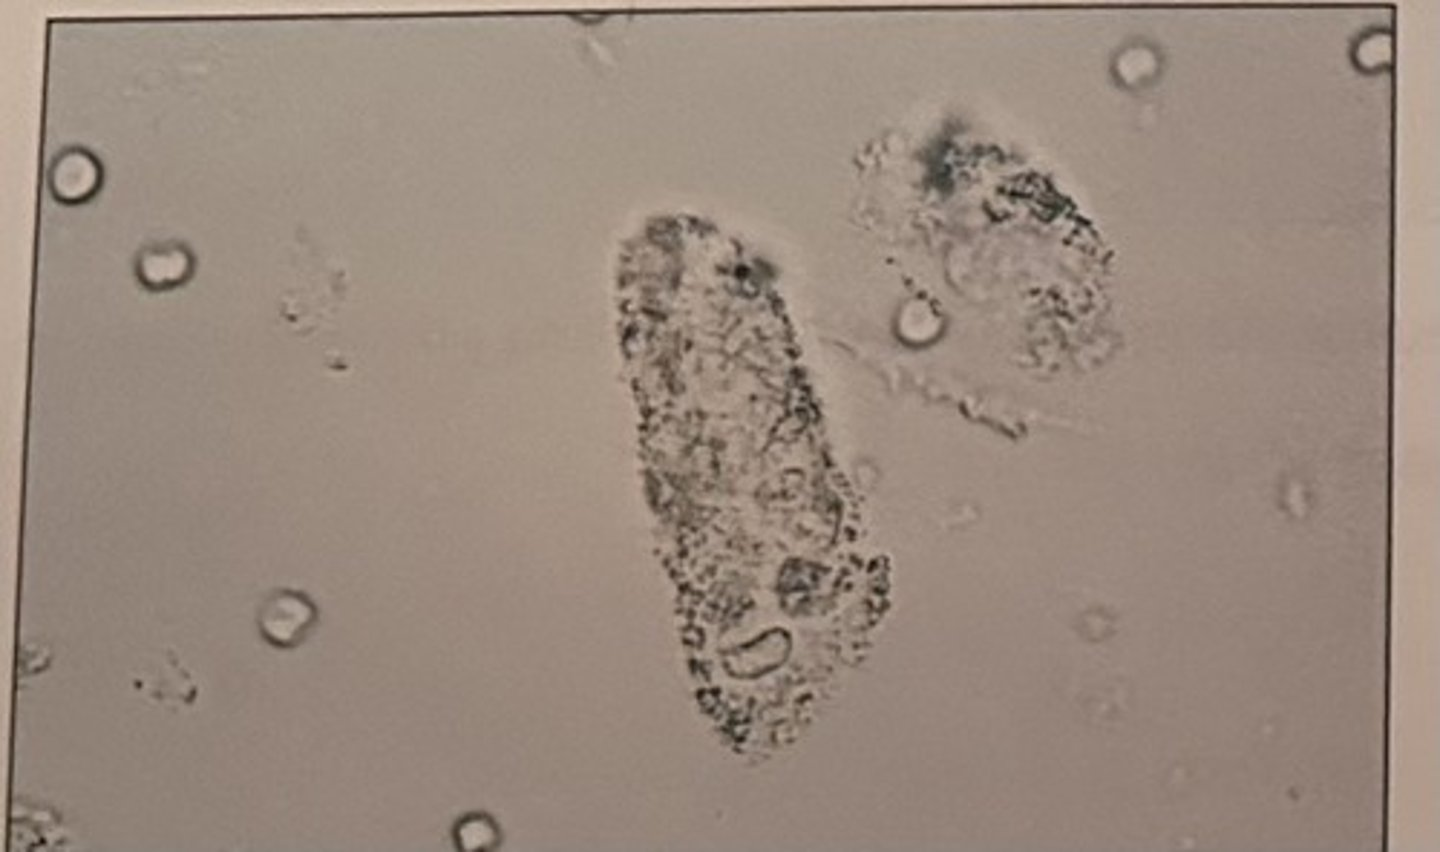

The centrifuged sediment for a random urine sample collected from a 17-year-old female patient is shown in the photomicrograph.

The reagent test strip is negative for leukocyte esterase and nitrite. The elements seen in the sediment are most likely the result of:

a. contamination

b. improper preservation

c. a UTI

d. chronic glomerulonephritis